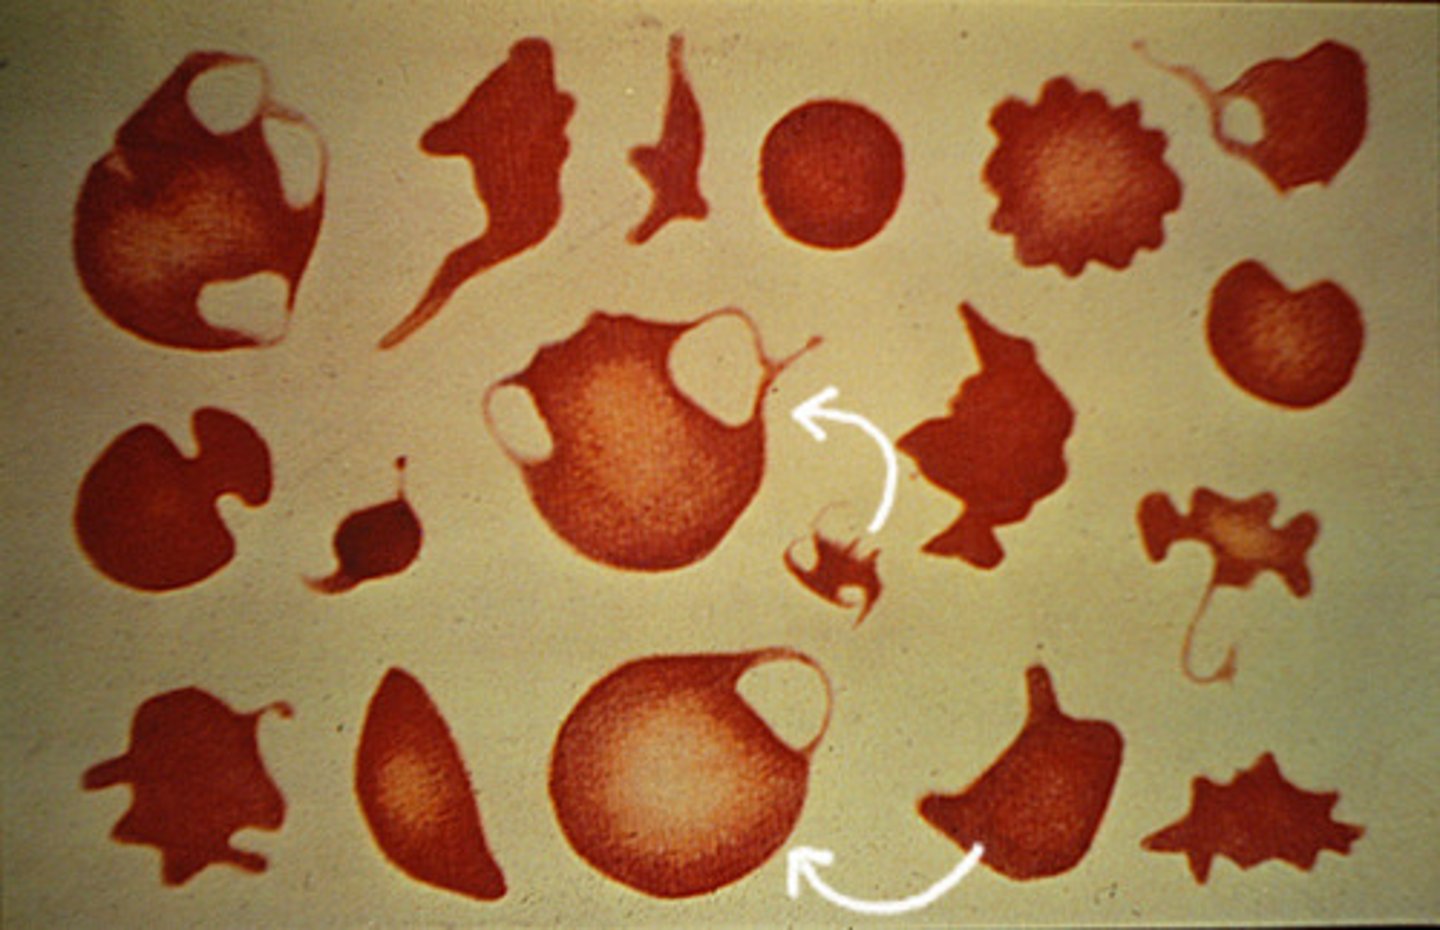

poikilocytosis

variation in the shape of RBC's

acanthocyte

MAMMAL

multiple (2-10), IRREGULARLY shaped and spaced fingerlike projections

- nickelodeon sign

schictocytes

RBC fragments

blister cells

small piece of RBC membrane formed a clear vesicle

keratocytes

one or 2 horn like projections

torocytes

AKA punched out cells

- "donut" hole presentation

--artifact

stomatocytes

RBC's have a linear area of central pallor